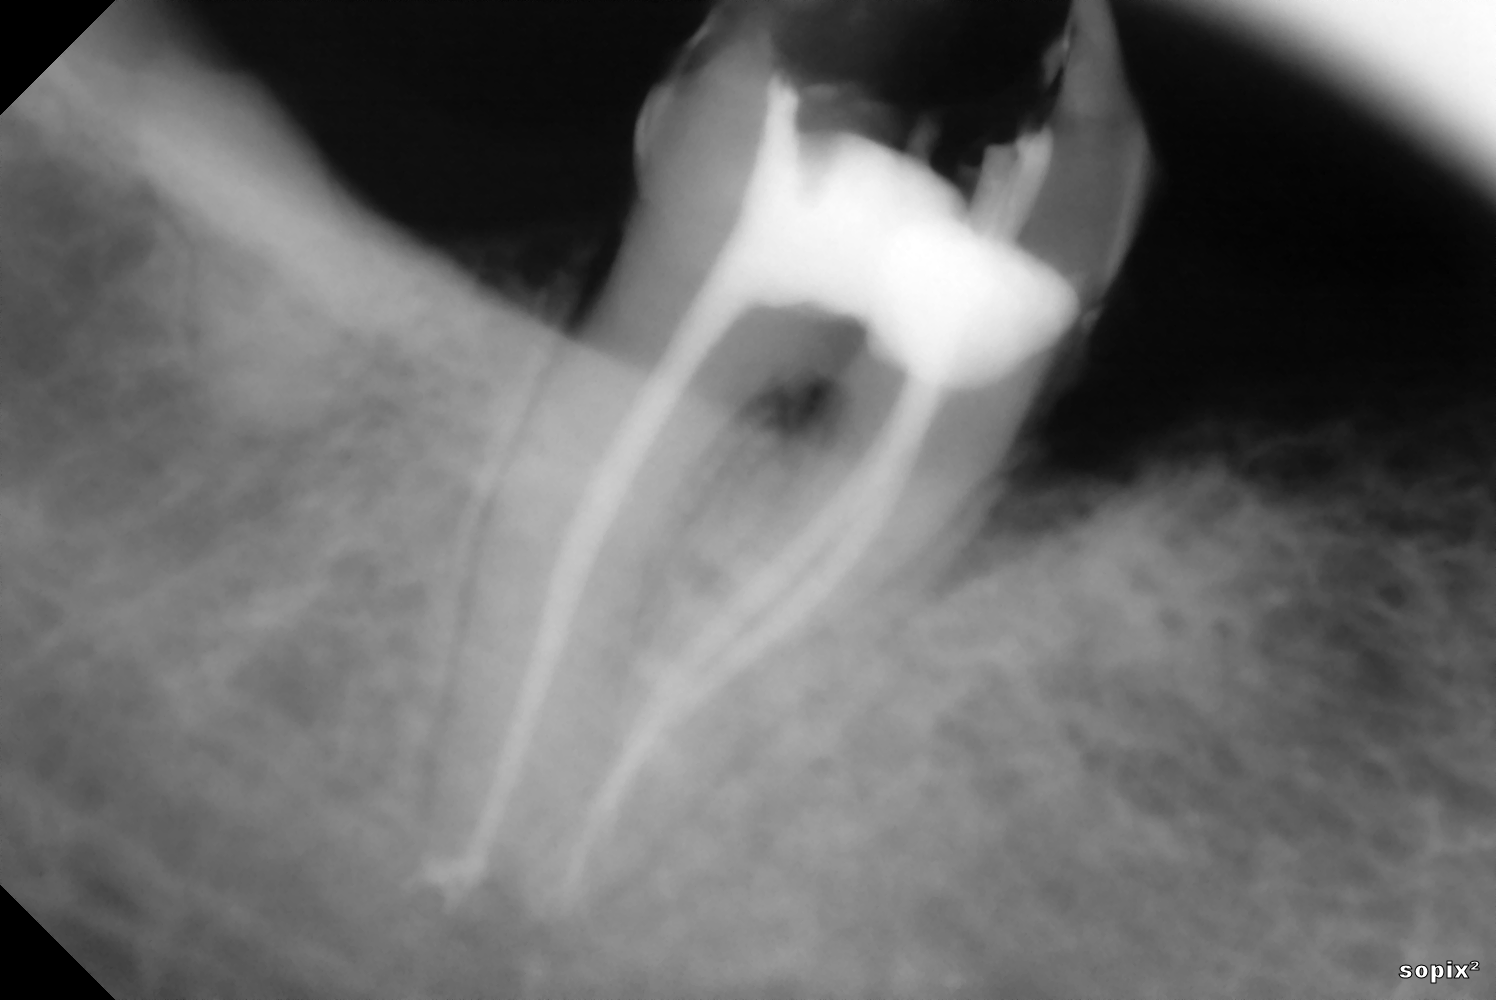

Η ενδοδοντική θεραπεία, η γνωστή απονεύρωση, αποτελεί πάντοτε μια πρόκληση που στόχο έχει να διατηρήσει το δόντι μέσα στο στόμα μας. |